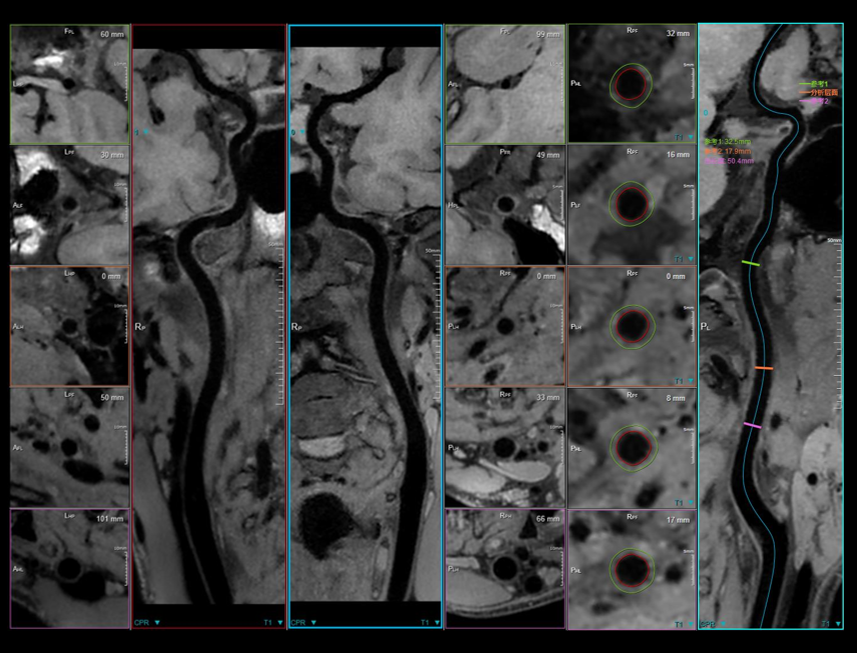

Technology Required for Ultra-wide Imaging

3.5MW의 최대 출력을 갖춘 차세대 GPA.

45mT/m 및 200 T/m/s의 그라디언트 성능.

0.029ppm @30 DSV 균일성 (일반적인 값).